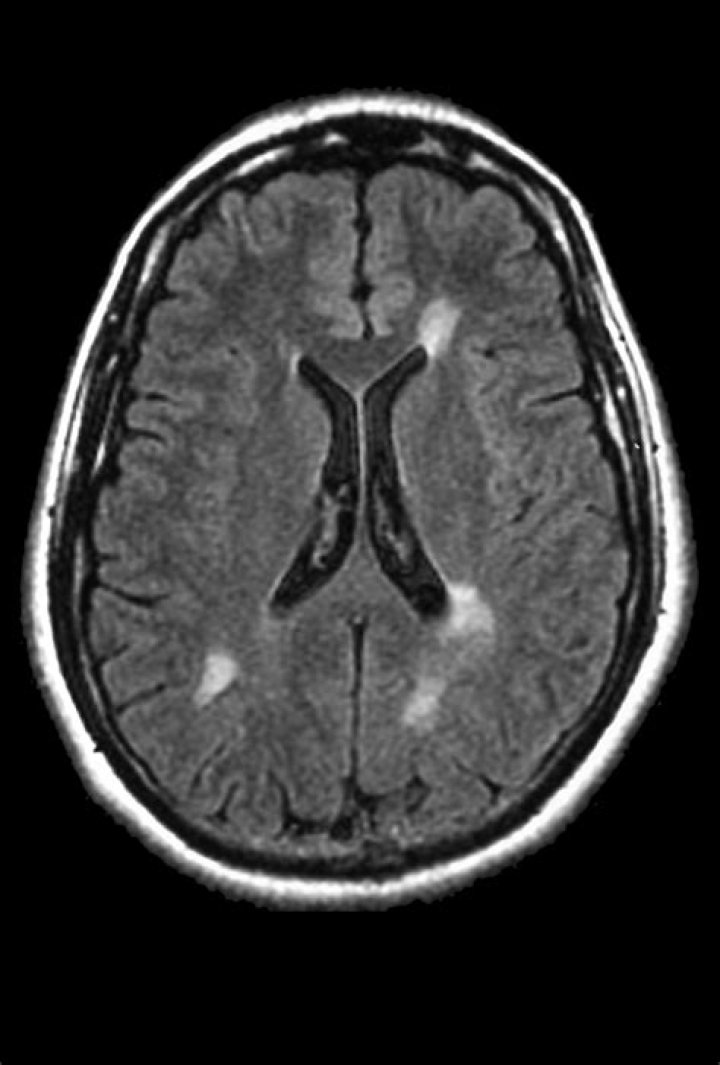

Magnetic resonance imaging has become the single most useful test for the diagnosis of MS; MRI is sensitive to brain changes which are seen in MS. Classically, the MRI shows lesions in the white matter deep in the brain near the fluid spaces of the brain (the ventricles).

What will an MRI show if you have MS?

It can show whether there's any damage or scarring of the myelin sheath (the layer surrounding your nerves) in your brain and spinal cord. Finding this can help confirm a diagnosis in most people with MS. A standard MRI scanner is like a large tube or tunnel.